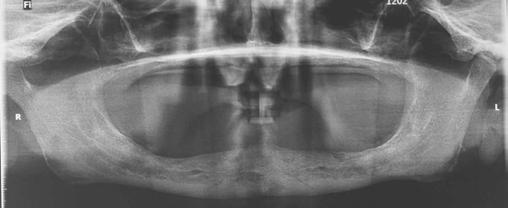

A 59-year-old male reported to the dental office with missing maxillary teeth due to poor oral hygiene. Treatment planning was done for All-on-4 implant placements followed by prosthesis. A complete medical history was obtained and was negative for any significant medical problems. The patient denied being allergic to any medication as well. The patient agreed to the implant placement and was advised to have an orthopantomogram (Figure 1).

Figure 1: Pre-op panoramic radiograph

Figure 5: Panoramic radiograph following implant placement